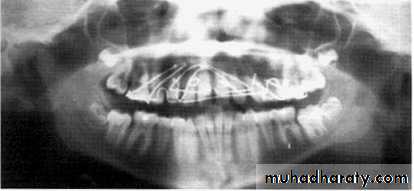

Patient is biting too far back

on rod or not at all

Anterior teeth blurry and wide,

ghosting of mandible and spine,

condyles close to edge of image

Patient too far back; note ghosting of mandible and spine, condyles pushed to outside of film, blurring and widening of anterior teeth